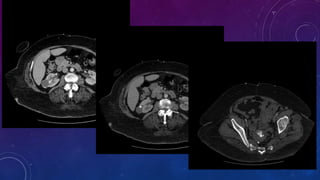

PRE TRANSPLANT

EVALUATION

VAS DEFERENS CALCIFICATION

CASE 2

• Failed kidney transplant

• Seminal vesicle / vas deferens calcification

FAILED BILATERAL RENAL TRANSPLANTS

CALCIFICATION